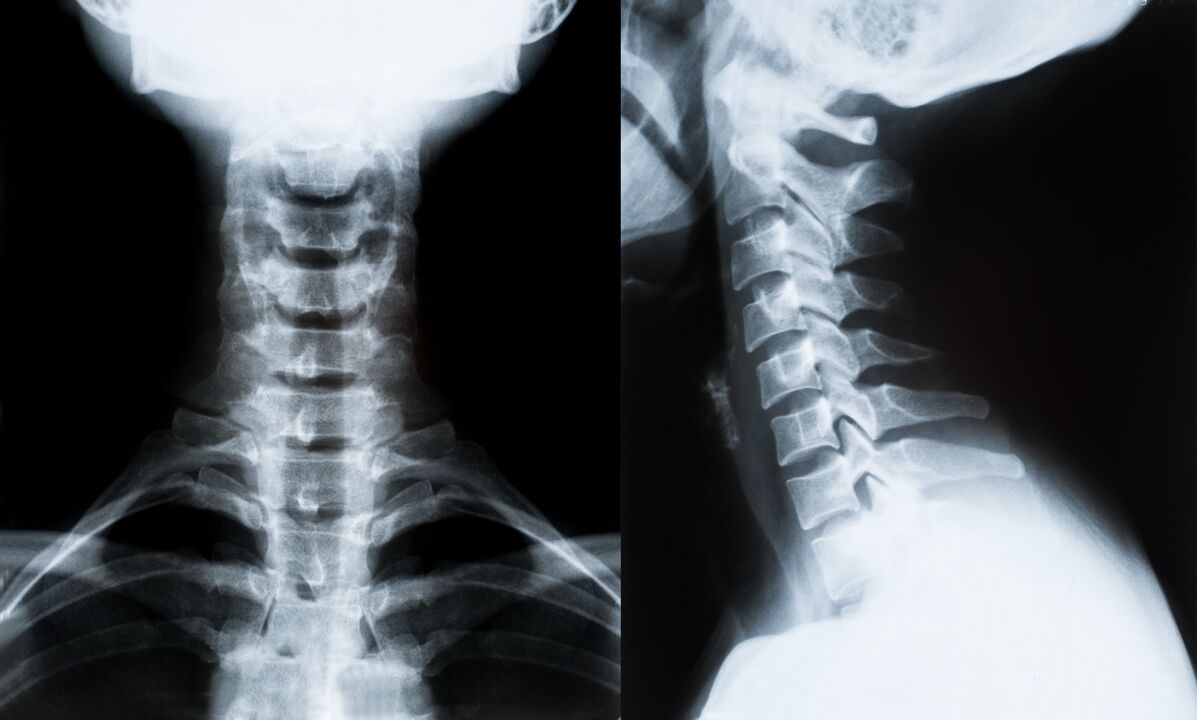

Hlavní metody diagnostiky a dalšího stanovení léčby osteochondrózy krční páteře:

- Rentgen. Nejméně účinná, ale tradiční diagnostická metoda.

- Magnetická rezonance je nejúčinnější diagnostickou metodou. Při tomto typu vyšetření pacienta jsou viditelné všechny potřebné struktury.

- Pokud je třeba změřit změny, použije se počítačová tomografie. Určuje přítomnost kýly a dalších věcí.

- Poslední metodou je ultrazvukové duplexní skenování. Tato metoda výzkumu určuje rychlost průtoku krve v tepnách.

Je nemožné přesně určit onemocnění páteře doma.